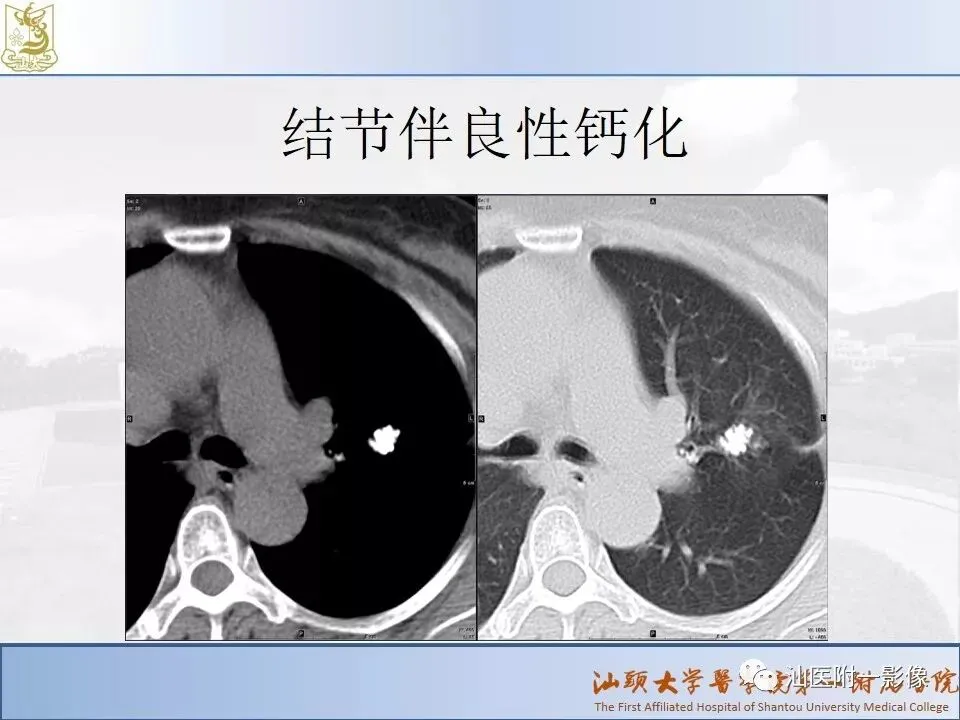

肺结节分类、处理及浅识肺结节分类影像报告和数据系统(Lung-RADS)

来源:汕医附一影像

说明:本课程病例主要来源于本院病例及参考资料,

无涉及病人隐私,仅做教学用途。